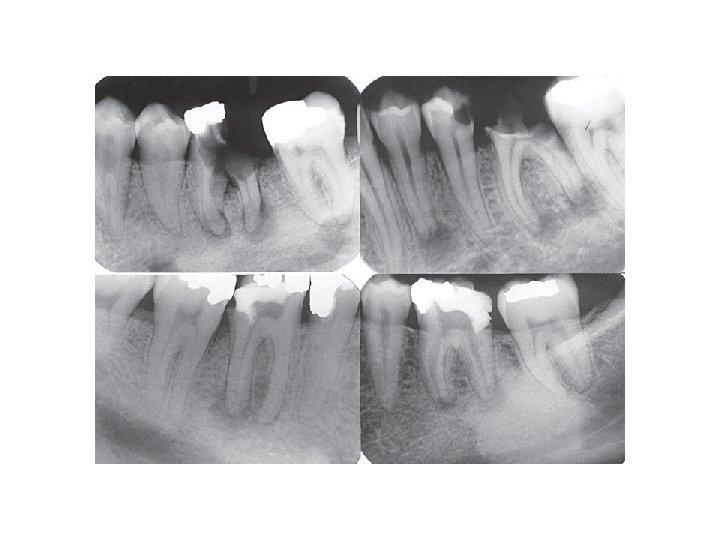

Wurzelbehandlung

Vor der Wurzelbehandlung Nach der Wurzelbehandlung